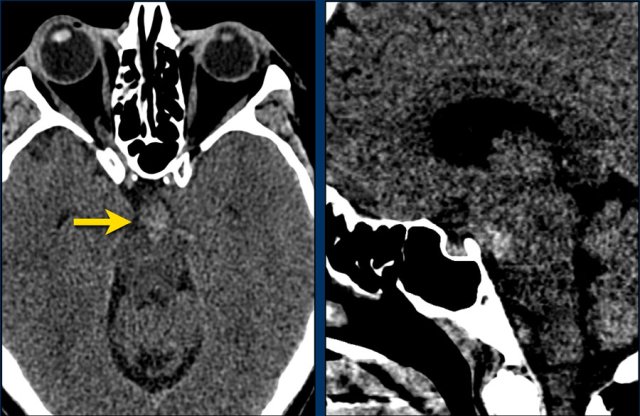

This patient presented with a cerebellar hemorrhage.

The gradient echo-images show multiple microbleeds.

This can be the result of long standing hypertension due to the central location of some of the microbleeds.

These small hemorrhages are also called microbleeds.

Notice how numerous these small hemorrhages are and primarily located in the perifery of the brain.

This patient presented with a cerebellar hematoma.

Continue with the T1W-image...

The T1W-image shows a hyperintense hemorrhage (arrow).